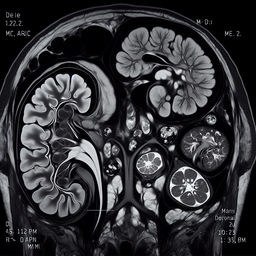

МРТ наднирників – це безпечний і неінвазивний метод діагностики, який використовує магнітне поле та радіохвилі для отримання детальних зображень надниркових залоз. Це дослідження допомагає виявити патології, такі як пухлини, крововиливи або вроджені аномалії.